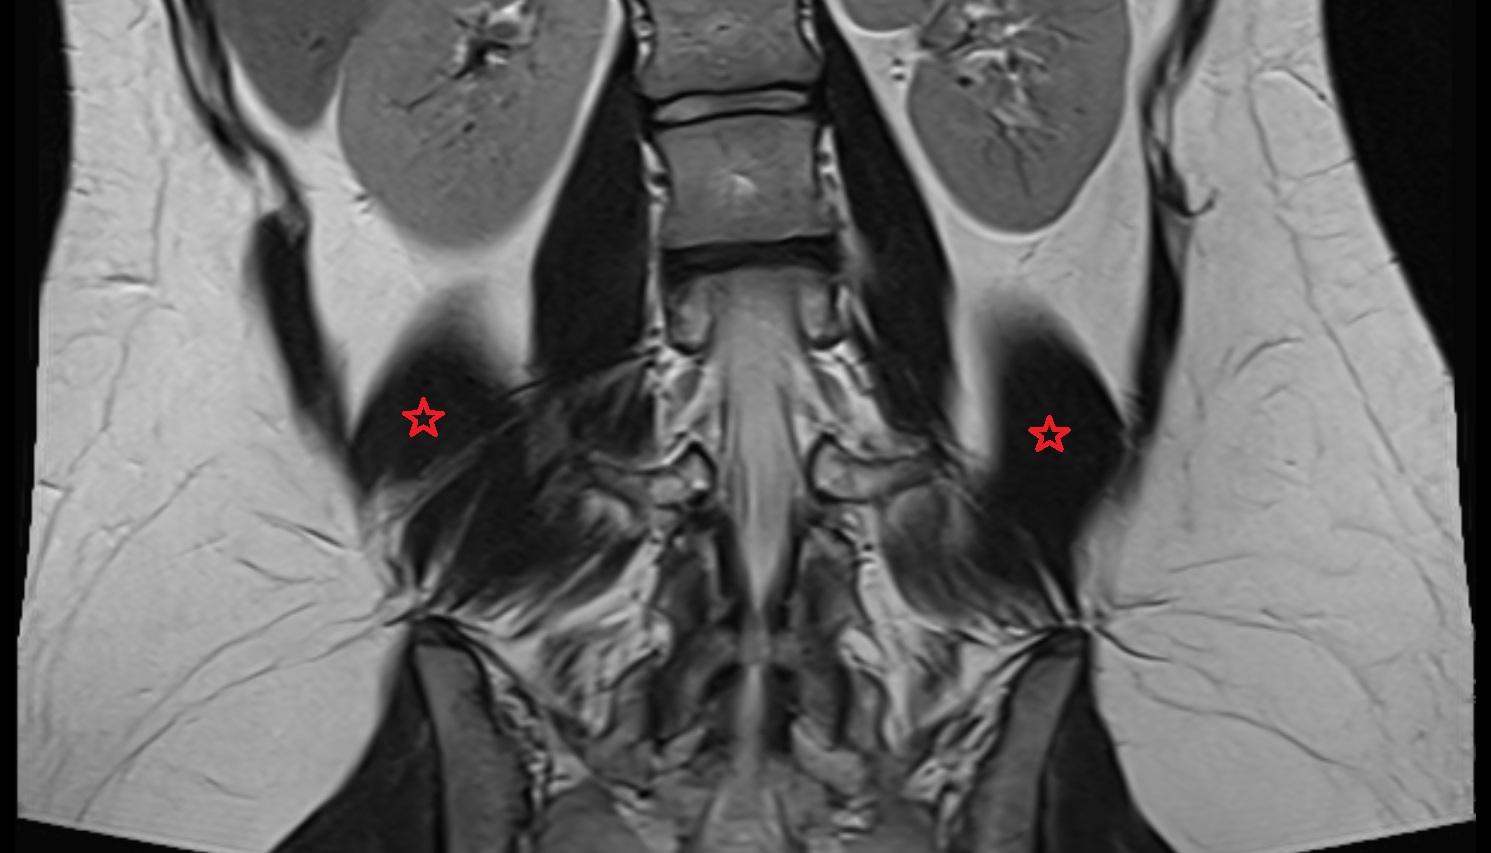

- Psoas major muscle

- Quadratus lumborum muscle

- Cauda equina

- Conus medullaris